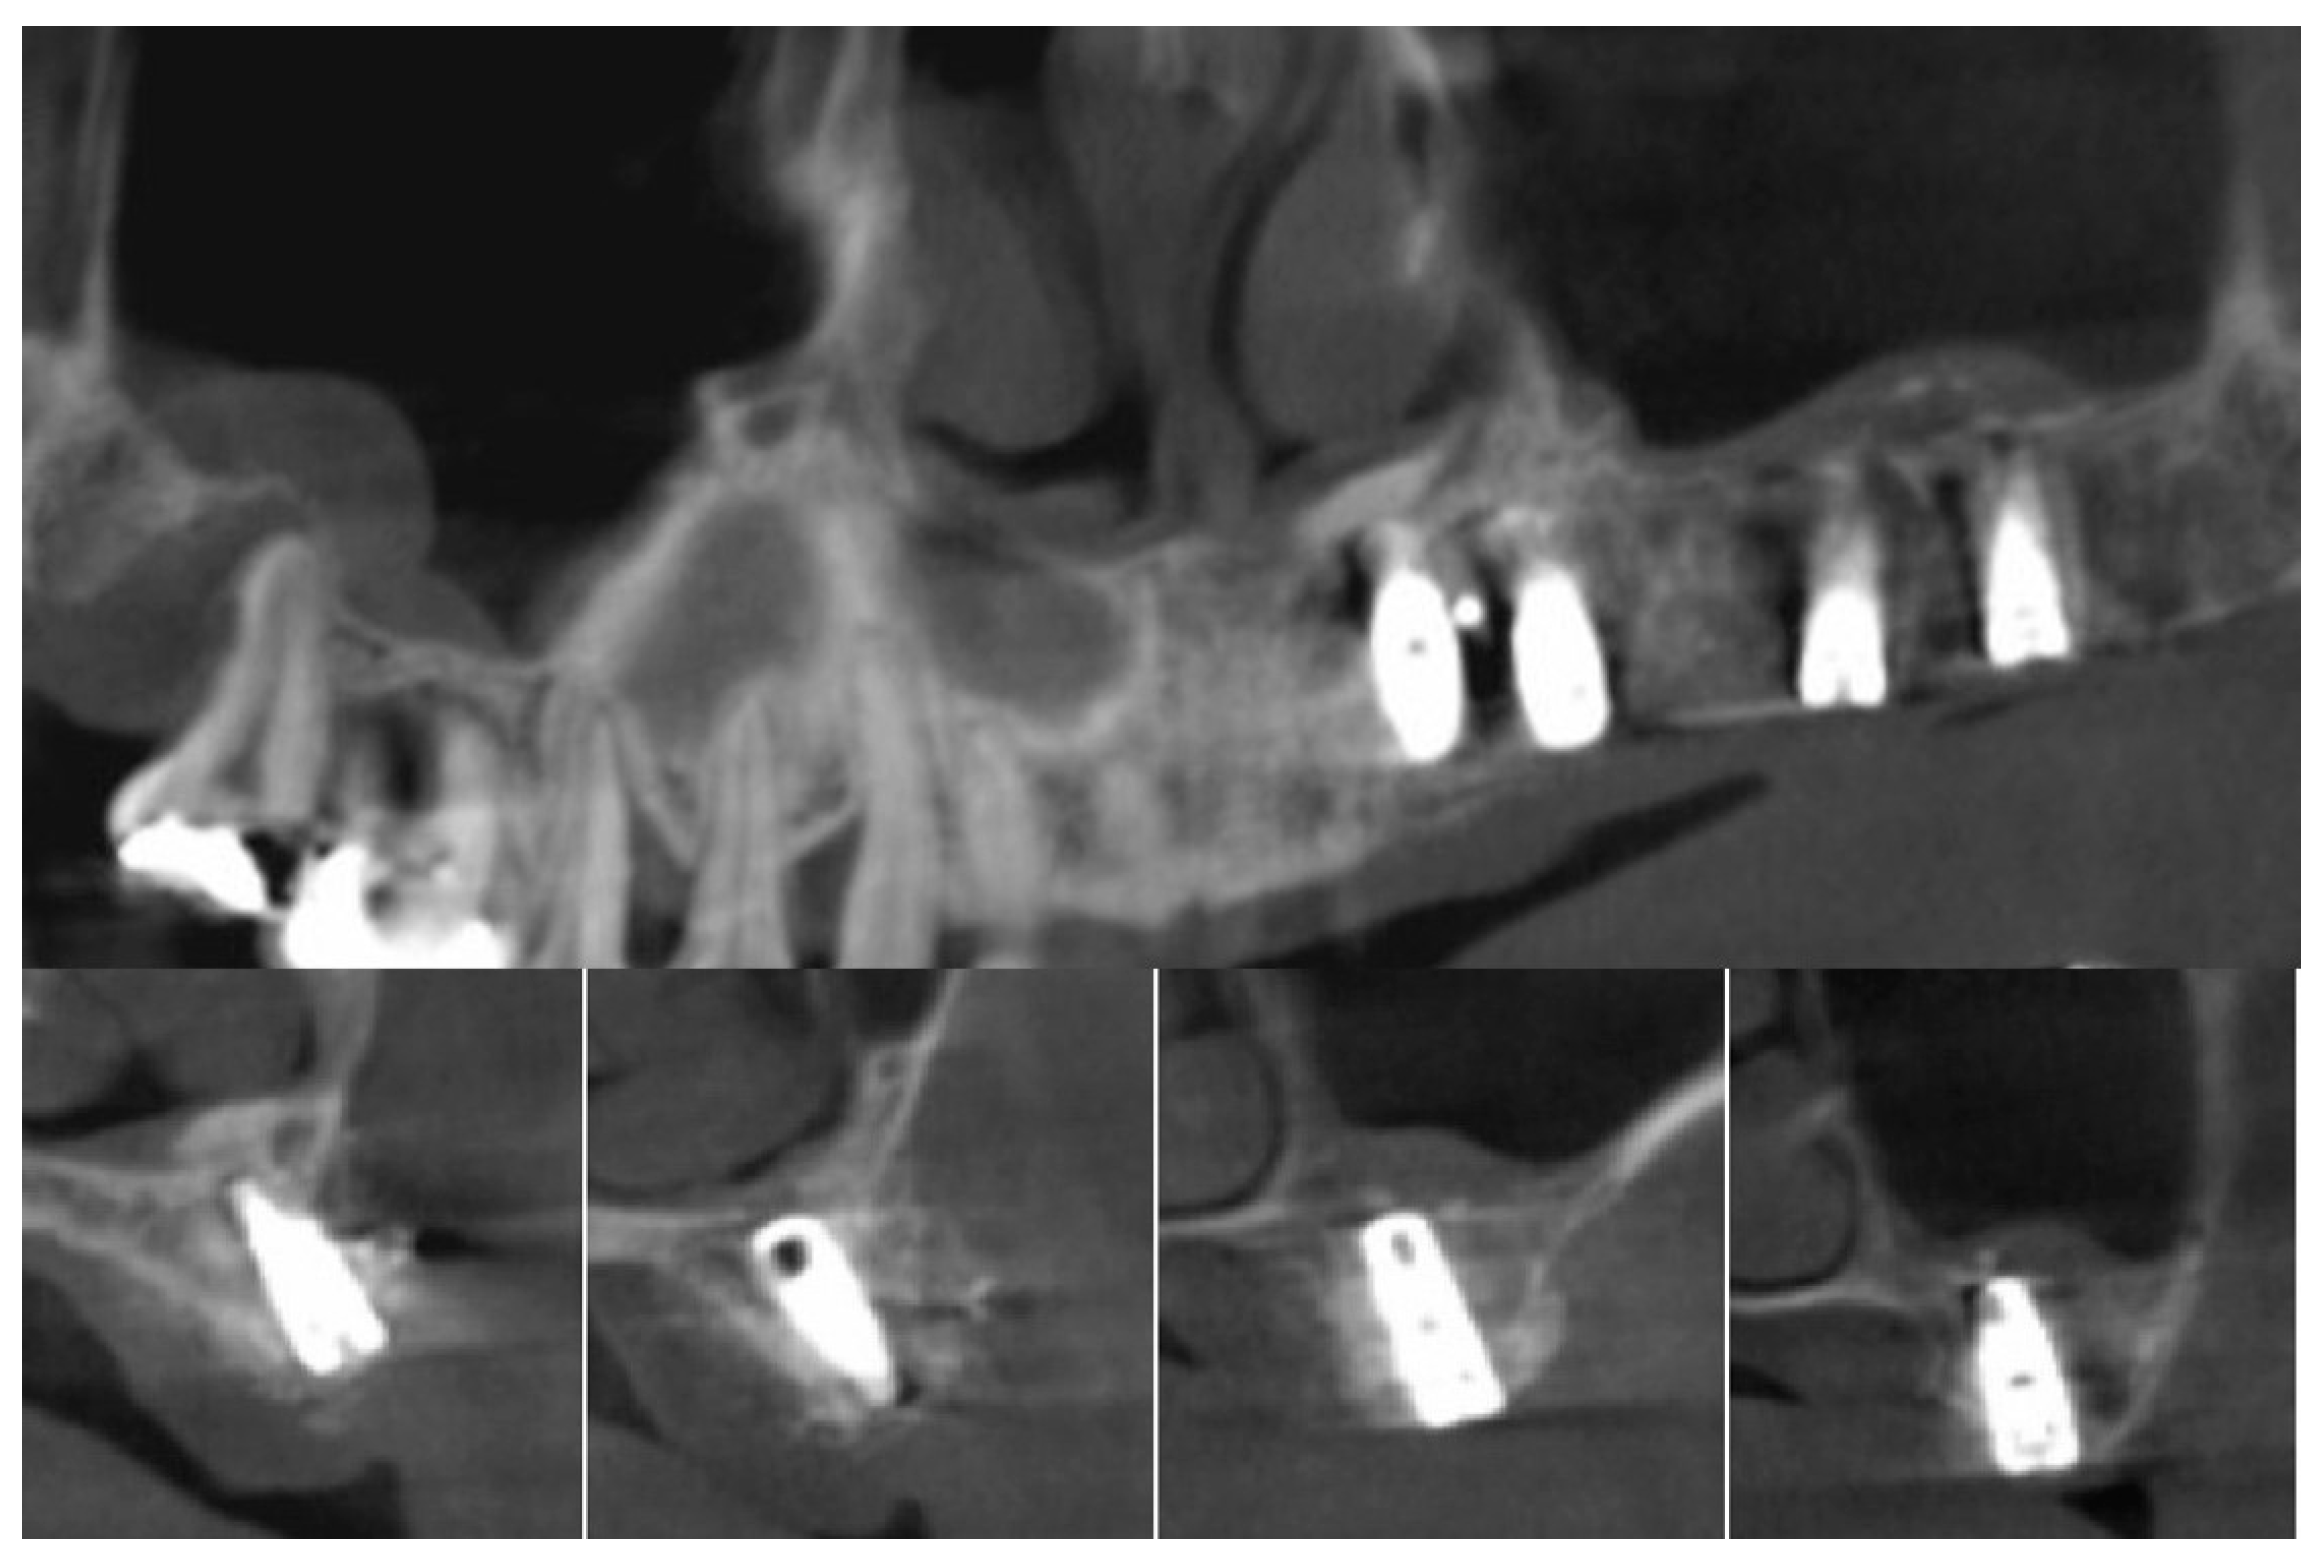

| 1 | #16 | 5 | 12 | 18 | 14 | 9 |

| 2 | #26 | 3 | 18 | 17 | 13 | 10 |

| 3 | #27 | 5 | 16 | 16 | 14 | 9 |

| 4 | #14,15,16,17 | 5,3,5,5 | 22 | 15,18,14,16 | 15,16,14,14 | 10,13,9,8 |

| 5 | #26,27 | 4,4 | 16 | 16,16 | 15,12 | 11,8 |

| 6 | #26 | 6 | 16 | 18 | 20 | 14 |

| 7 | #17 | 2 | 24 | 16 | 15 | 13 |

| 8 | #27 | 2 | 22 | 19 | 18 | 16 |

| 9 | #16 | 2 | 22 | 16 | 14 | 12 |

| 10 | #16,26 | 3,3 | 23 | 23,20 | 20,22 | 17,19 |

| 11 | #26,27 | 3,2 | 24 | 19,18 | 20,16 | 17,14 |

| 12 | #27 | 4 | 22 | 16 | 15 | 11 |

| 13 | #16 | 5 | 12 | 14 | 14 | 9 |

| 14 | #26 | 4 | 16 | 12 | 12 | 8 |

| 15 | #16 | 1 | 20 | 22 | 18 | 17 |

| 16 | #17 | 5 | 13 | 17 | 20 | 15 |

| 17 | #26,27 | 6,6 | 15 | 10,11 | 15,16 | 9,10 |

| 18 | #27 | 3 | 25 | 12 | 14 | 11 |

| 19 | #26,27 | 1,2 | 20 | 21 | 14,14 | 13,12 |